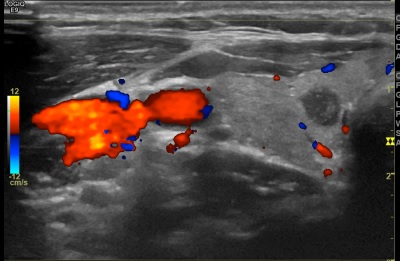

상기환자 외부건강검진이상소견으로 내원하신 40대초반 여성분으로 의심스러운 갑상선 우엽 결절 세포검사진행후 갑상선암으로 진단되었습니다